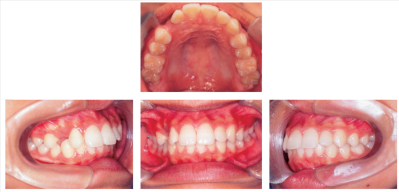

12歳の男児。上顎歯列の空隙を主訴として来院した。初診時の口腔内写真、エックス線写真及び矯正材料の写真を別に示す。上顎右側犬歯の歯冠近遠心幅径の予測値から、上顎のarchlength discrepancyは-2mmである。3⏌の開窓後、マルチブラケット装置を用いて非抜歯で治療を行うこととした。